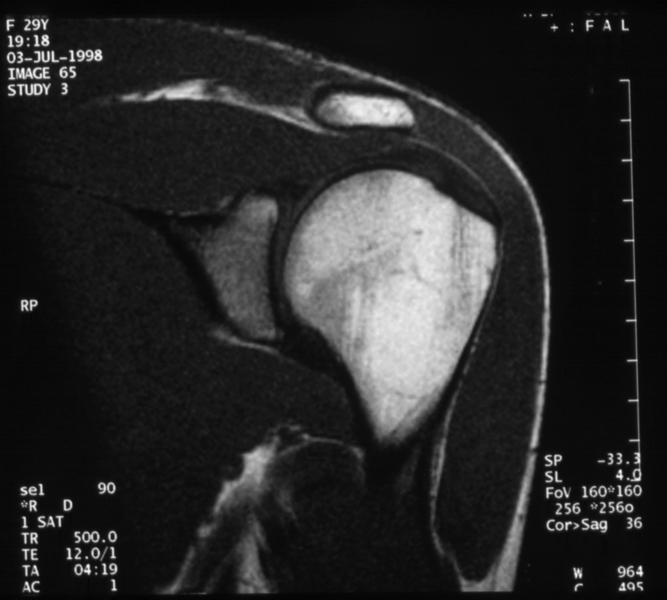

Radiology MS 196 - Normal MR of the Left Shoulder

Identify: Coronal - humeral head, acromion, glenoid, deltoid muscle, supraspinatus muscle, supraspinatus tendon